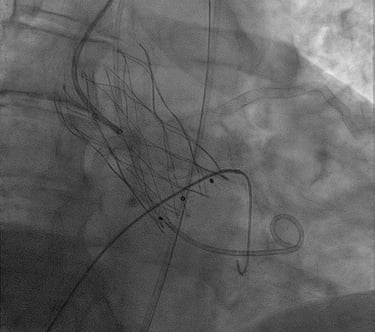

ANGIOPLASTICA

Angioplastica coronarica e lo stent

Si tratta del piu' comune trattamento attualmente utilizzato per curare l'aterosclerosi coronarica. E' una metodica che si avvale di molteplici strumenti appositamente ideati e realizzati e puo' essere effettuata subito dopo la coronarografia, utilizzando la stessa via di accesso arterioso. Solitamente, il paziente sottoposto ad angioplastica coronarica programmata puo' essere dimesso il giorno successivo alla procedura. Lo stent coronarico e' un dispositivo di grandezza millimetrica, in lega metallica biocompatibile (quindi senza fenomeni di rigetto), che viene utilizzato di solito dopo la dilatazione dell'arteria coronarica con il palloncino, per mantenere la pervietà della arteria.